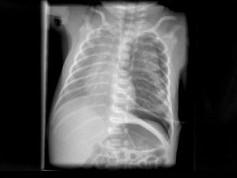

出生一天的早产儿,呼吸窘迫,请结合图片选出最可能的诊断 ( )A、肺气肿B、气胸C、肺气肿D、肋骨骨折E、湿肺

问题 出生一天的早产儿,呼吸窘迫,请结合图片选出最可能的诊断 ( )

选项 A、肺气肿 B、气胸 C、肺气肿 D、肋骨骨折 E、湿肺

答案 B